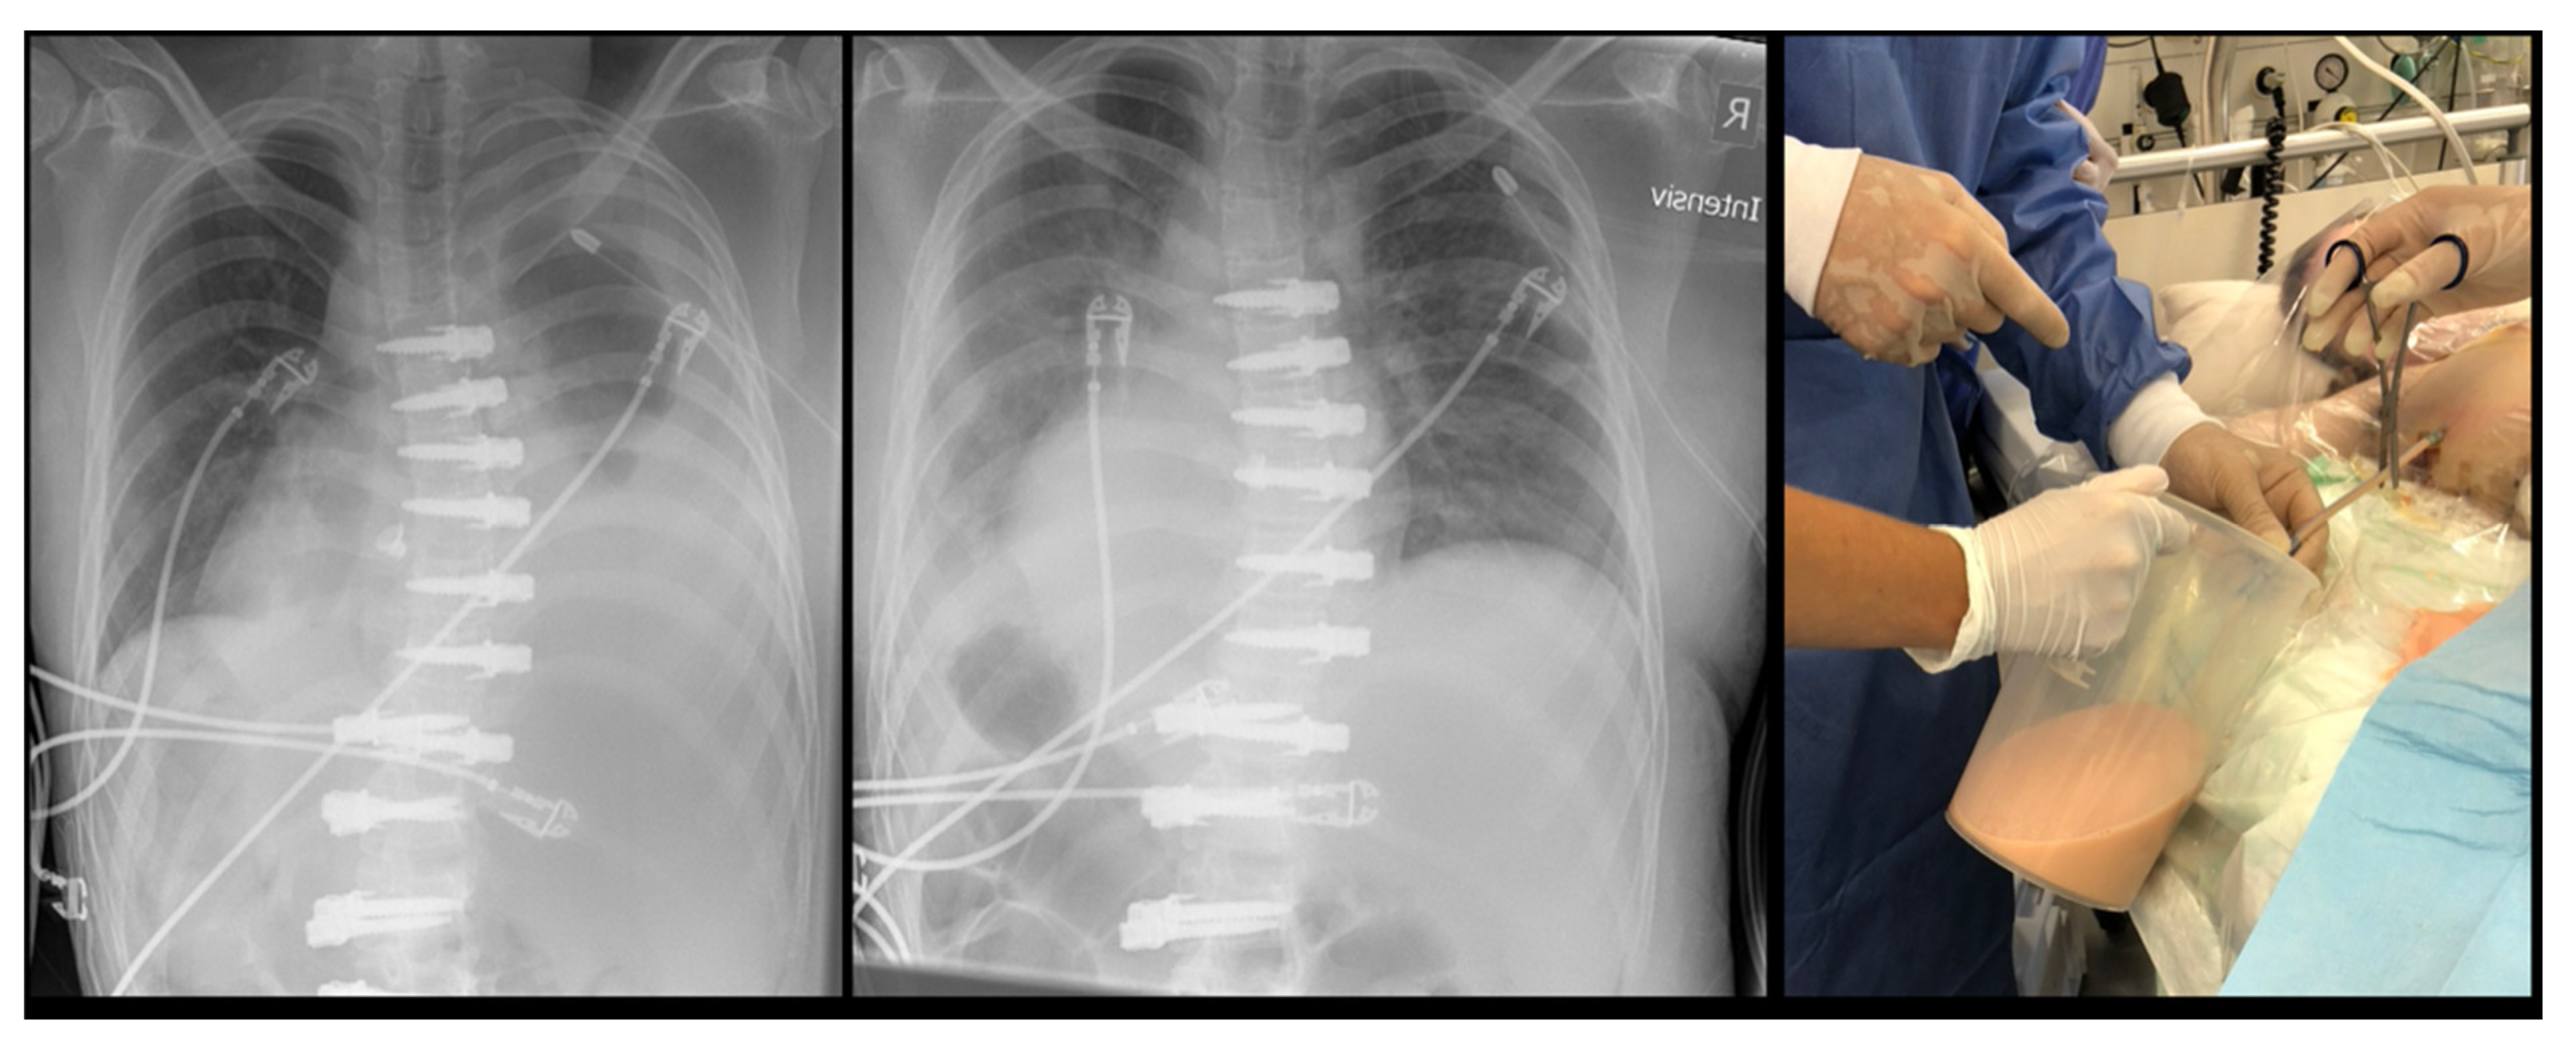

| 3 | 16.2 | F | 4 | T5-T12 right | Contralateral atelectasis | 2 days | Left | Severe dyspnea | Re-intubation for 3 days, 3 bronchoscopies and removal of a mucus plug |

| 10 | 14.3 | F | 1 | T11-L4 left | Pleural effusion with concomitant infection | 3 weeks | Left | Sudden sharp pain in the left chest and dyspnea | Attempted aspiration and chest tube without output. VATS and six weeks antibiotitcs because of postivie culture for staph epidermidis |

| 11 | 12 | F | 4 | T5-T11 right | Haematothorax | 1 day | Right | No symptoms, significant blood loss noticed after declamping the chest tube and drop of haemoglobin levels | Emergency explorative thoracotomy using the same surgical approach. No active bleeding found but clotted hematoma |

| 12 | 13 | F | 2 | T6-T12 right T12-L4 left | Haematothorax | 6 weeks | Right | Acute chest pain | Emergency explorative thoracotomy |

| 13 | 16.5 | M | 1 | T10-L4 left | Pleural empyema | 5 weeks | Left | Dyspnea, elevated CRP levels | VATS and antibiotic therapy |